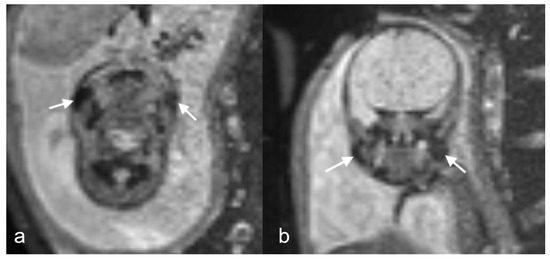

Figure 2.

(a,b) Coronal TRUFI MRI in a 23-week fetus, one of dichorionic diamniotic twins, demonstrating bilateral symmetric, oval low-signal-intensity fat pads (black arrows) corresponding to (c) T1 VIBE hyperintensity (white arrow).